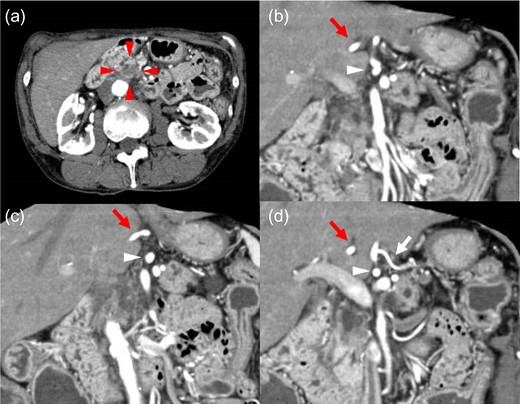

Axial and reconstructed coronal contrast-enhanced CT. (a) Axial contrast CT image showing a 17 × 12 mm hypovascular tumor in the pancreatic head (red arrowhead). No enlarged lymph nodes or distant metastases were detected. (b–d) Coronal contrast CT image showing the CHA (red arrow) forming a common trunk (white arrowhead) with the LGA (white arrow) and coursing within the lesser omentum. CHA: common hepatic artery. LGA: left gastric artery.